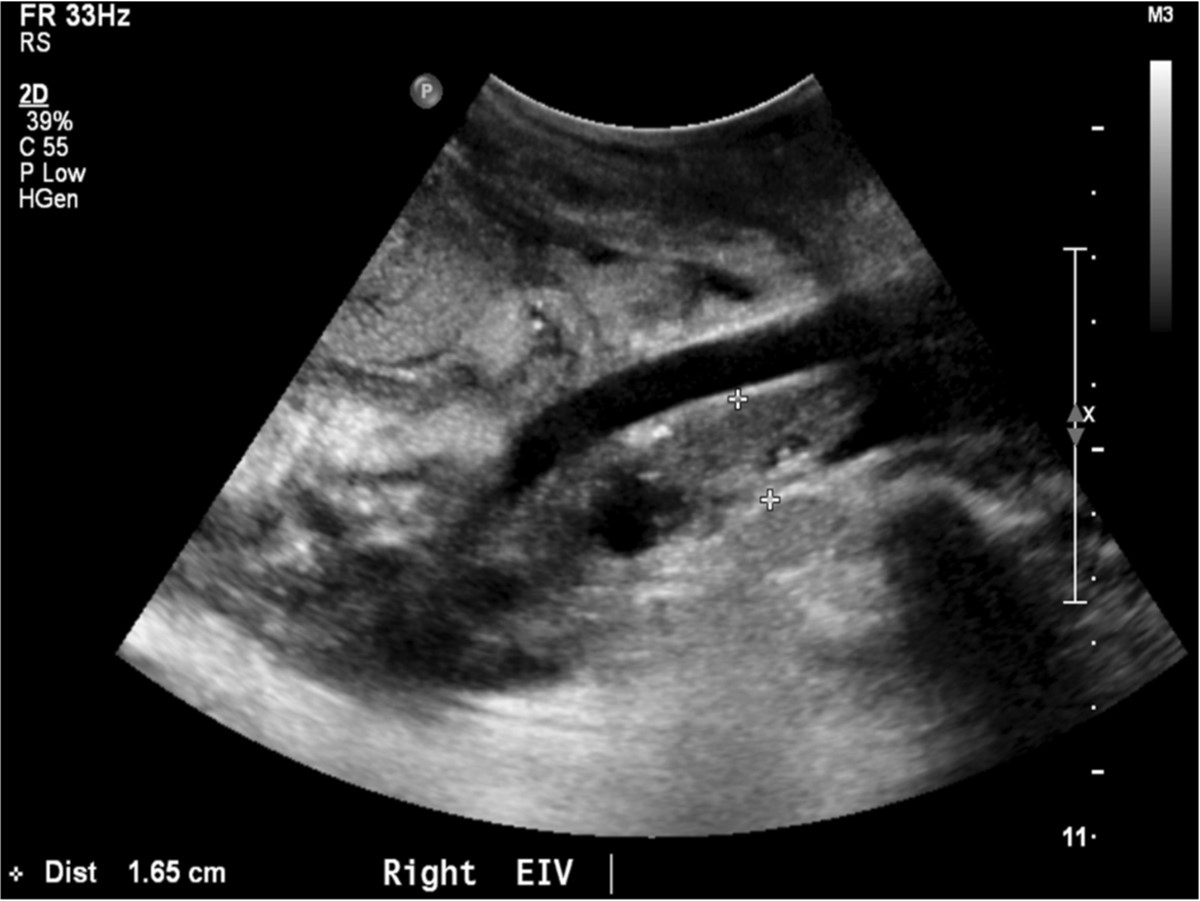

수술 직후 시행한 doppler US소견에서는 renal artery and vein에 flow abnormality가 없었으나, 수술 받은 뒤 약 20일 경에 시행된 doppler ultrasonography 상 right external iliac vein 전체가 thrombus로 인하여 total occlusion되어 있었다. Right common femoral vein 내부에도 massive thrombus로 인한 near total occlusion 상태로 partial flow를 유지하고 있었다(Fig. 1).

Fig. 1.

Fig. 1. Ultrasonography demons tated completely occlusive thrombus with in the right external iliac vein.